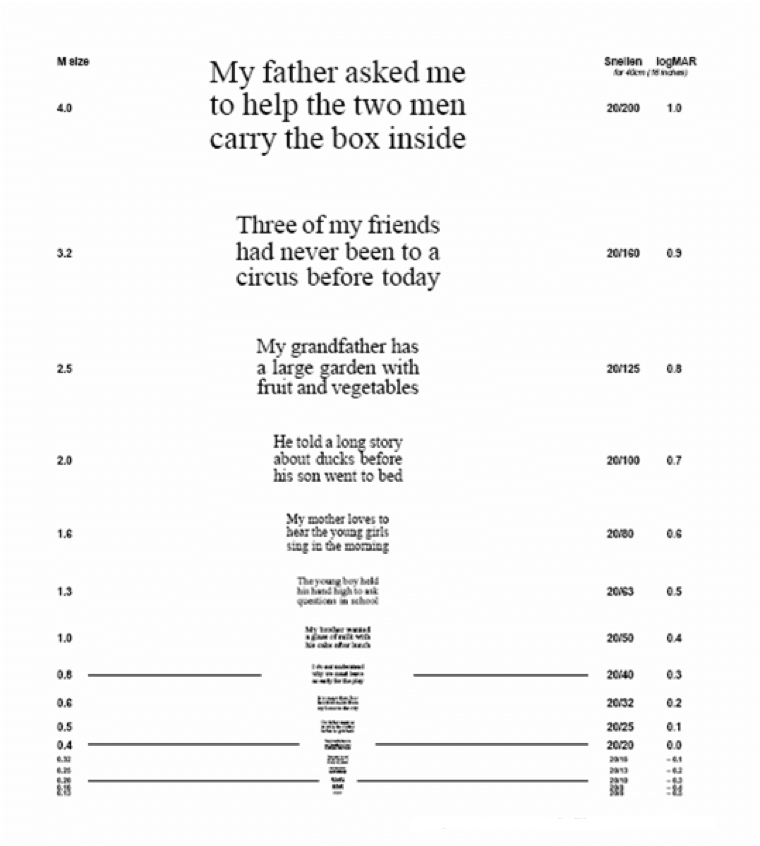

El principal síntoma que experimentan las personas con DMAE es la pérdida de visión. Por lo tanto, la DMAE suele diagnosticarse mediante un examen ocular rutinario. Un examen completo de agudeza visual mide la capacidad de una persona para ver detalles, formas y letras a una determinada distancia.3 La agudeza visual mejor corregida se evalúa normalmente utilizando una tabla de Snellen, pero tenga en cuenta que su profesional sanitario también puede utilizar otras tablas. El número de letras que una persona puede identificar correctamente representa su agudeza visual. Dicho de otro modo, cuanto más abajo en la tabla de Snellen pueda leer una persona, mejor será su agudeza visual.3

La tabla de agudeza ¨MNRead¨ o tabla de lectura de baja visión de Minnesota

En la vida cotidiana, la variedad de tamaños de los textos puede ser un gran reto para las personas con DMAE, ya que suelen desarrollar dificultades para mantener una buena velocidad de lectura. La tabla de agudeza ¨MNRead¨ mide la velocidad de lectura del individuo en relación con el tamaño de la letra. Una persona lee en voz alta frases en tamaños de letra decrecientes a partir de un gráfico. El punto en el que la velocidad de lectura disminuye con un tamaño de letra menor está correlacionado con su capacidad visual.